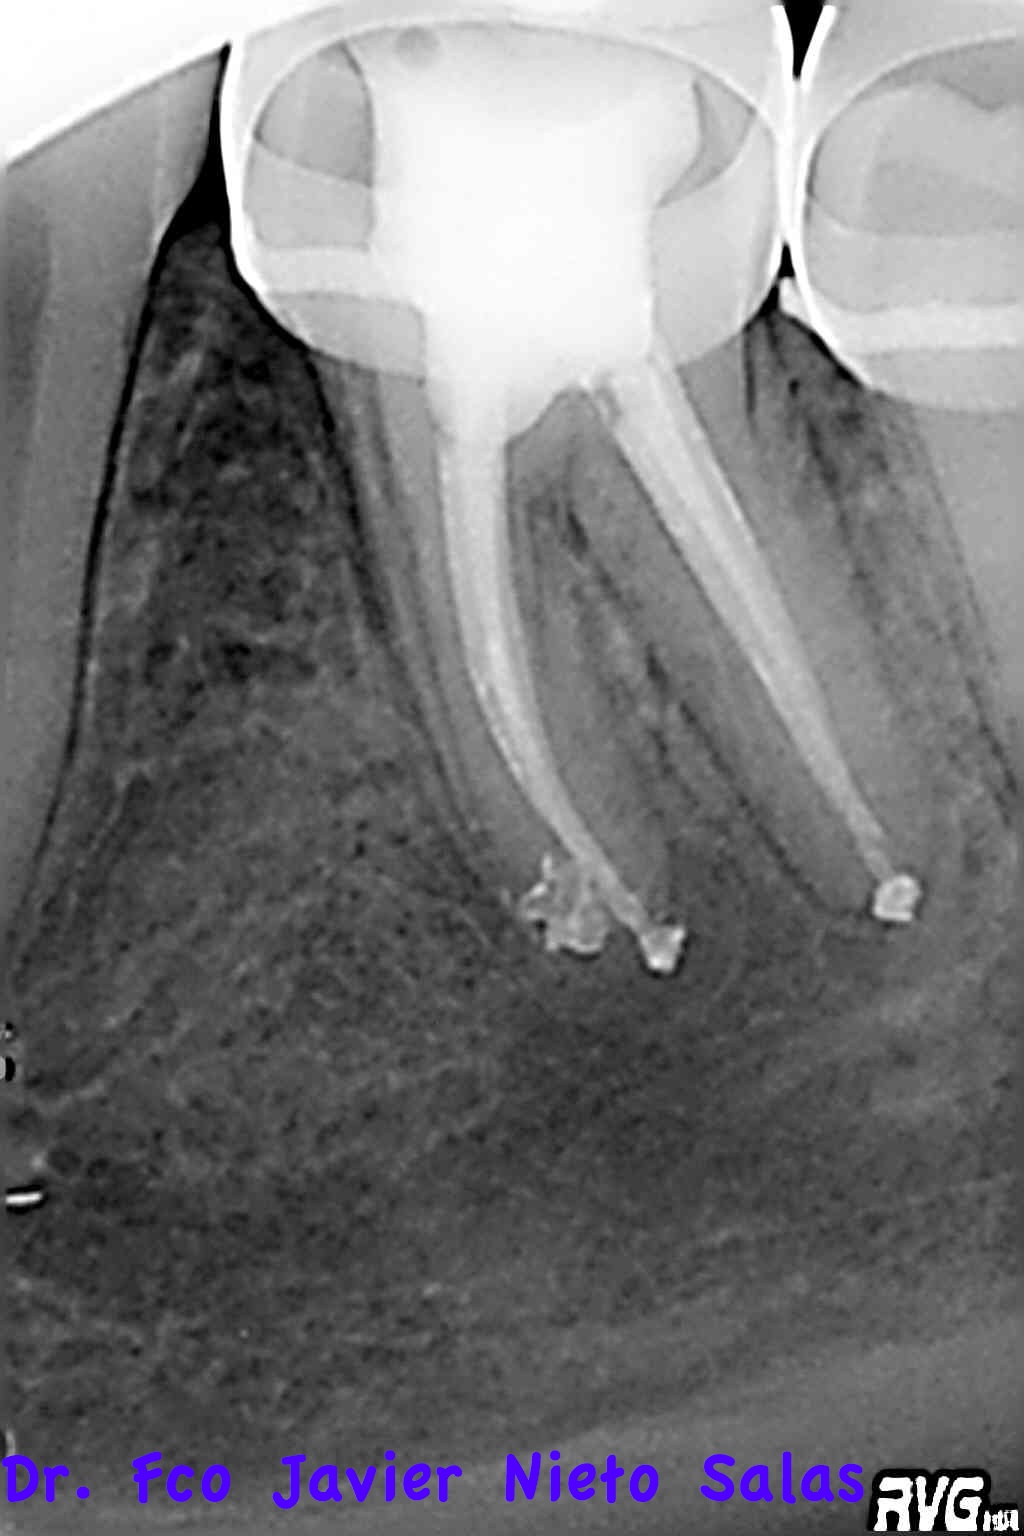

Nos llegó a revisión una chiquilla que se le realizó un tratamiento de conductos hace un año.

La paciente llegaba a la consulta con bandas de ortodoncia:

Presentaba una lesión periapical crónica, su diagnóstico es una necrosis pulpar con periodontitis apical crónica.

Le realizamos el tratamieto endodóntico del sistema de conductos en dos sesiones, soy un fiel defensor del medicameento intraconductos por varios motivos que quizás no sea el momento de comentar.

Usamos la técnica de ola continua de calor descrita por Buchanan y el backfilling se hizo con gutapercha inyectada.

Se citó a revisión a los nueve meses, no presentaba sintomatología y los signos claros de evolución positiva.